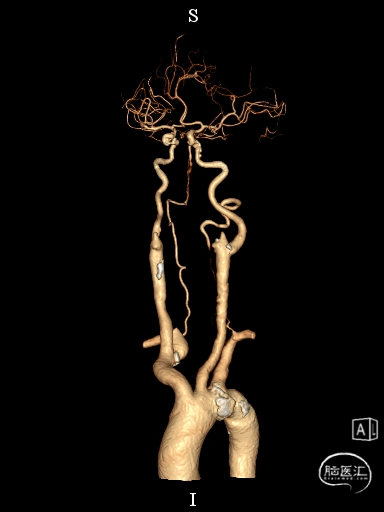

术后CTA:Bridge药物支架形态良好,前向血流良好。

术后半年CTA:Bridge支架形态及贴壁良好,前向血流正常。

术后造影:

血管再通,前向血流3级。左侧为胚胎型大脑后。